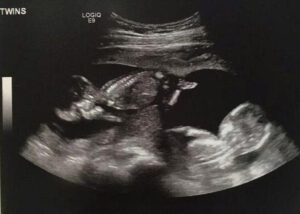

TEXAS— After months of relentless speculation and whispers that threatened to break the internet, Clare Duggar (née Spivey) and her husband, Justin Duggar, have finally broken their silence with an announcement that has left the entire Duggar fandom STUNNED! Forget the single-baby bumps—the Texas-based newlyweds are expecting TWINS!

Clare’s emotional social media post—which quickly went viral—not only confirmed the pregnancy but joyfully announced they were preparing for two new bundles of joy! While the specific genders remain a thrilling secret, the couple expressed profound gratitude for their miracle.